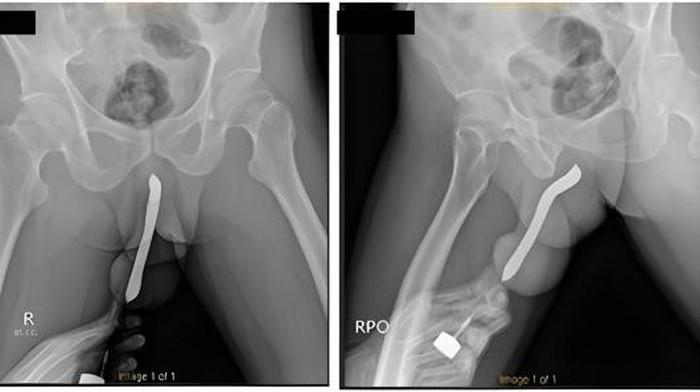

Kasus yang dipublikasikan di International Journal of Surgery Case Reports menyebut pria itu ke rumah sakit setelah sikat gigi yang ditancapkan ke alat vitalnya itu patah menjadi dua saat dia berhubungan seks.

Dokter kemudian melakukan operasi yang memakan waktu selama dua jam di RSU dr Soetomo Surabaya, Jawa Timur.

Dokter yang memeriksanya menyebut pria berusia 43 tahun itu sedang berhubungan seks dengan seorang wanita yang berada di atas saat kejadian mengerikan itu terjadi.

Saat ditanya bagaimana sikat gigi tersebut bisa masuk ke dalam penisnya, pria tersebut mengatakan benda tersebut dimasukkan ke dalam penisnya untuk kepuasan seksual.

Peristiwa yang terjadi tahun 2017 ini menyebut bahwa pria tersebut mengaku sebelumnya sempat membuat sayatan kecil untuk memasukkan sikat gigi.

"Pasien mengalami cedera penis saat melakukan hubungan seksual dengan posisi wanita di atas pada malam sebelumnya," demikian kata laporan jurnal tersebut.

"Dia mengalami 'kelainan bentuk terong', sebuah tanda patah tulang penis," lanjutnya.

Si pria itu dipulangkan tiga hari setelah operasi, dan melaporkan tidak ada masalah.

Dan dia kembali untuk pemeriksaan lanjutan 1 bulan kemudian setelah bisa buang air kecil dan mengaku tidak mengalami komplikasi apapun.